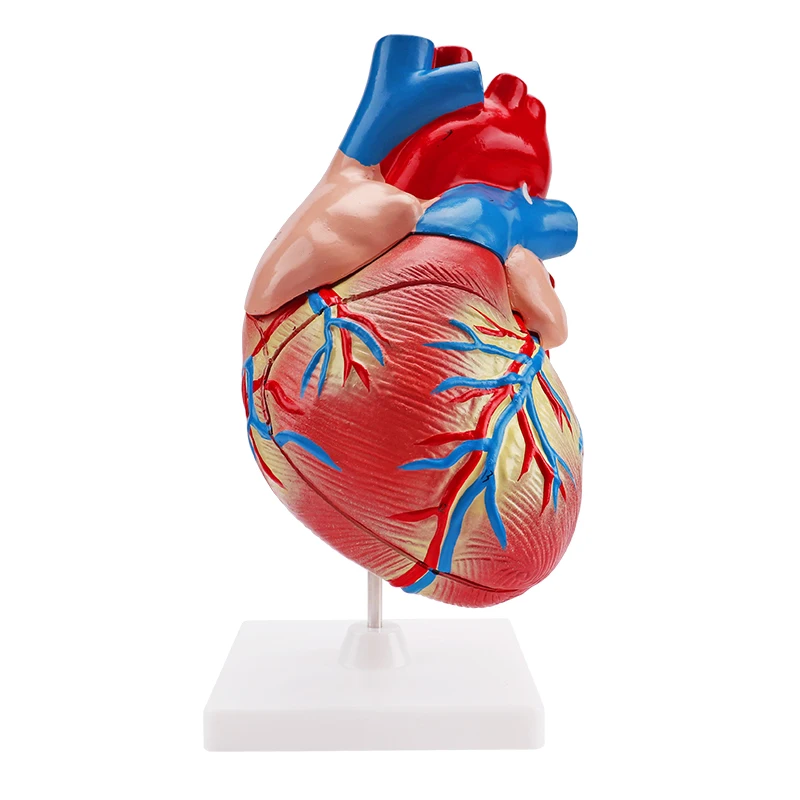

Фотографии и 3D-модели анатомии сердца человека